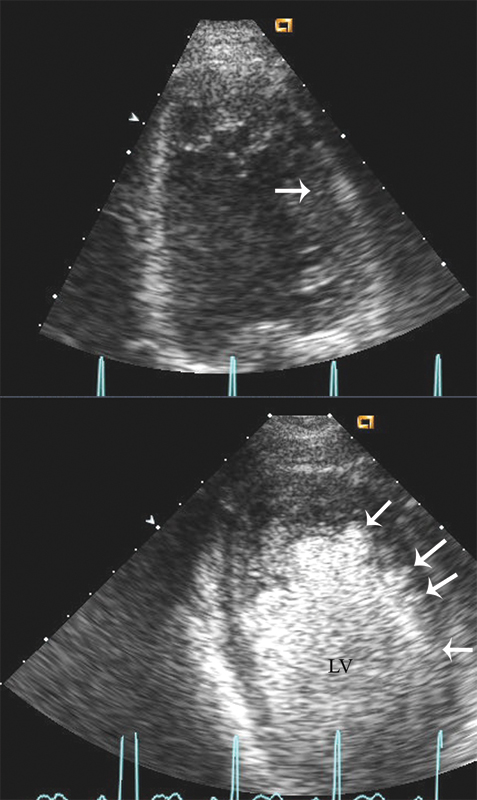

فحوصات تشخيصية لبعض امراض القلب والشرايين التاجية